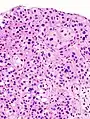

Histopathology of transitional carcinoma of the urinary bladder. Transurethral biopsy. Hematoxylin and eosin stain.

Transitional refers to the histological subtype of the cancerous cells as seen under a microscope.

The 1973 WHO grading system for transitional cell carcinomas (papilloma, G1, G2 or G3) is most commonly used despite being superseded by the 2004 WHO[14] grading for papillary types (papillary neoplasm of low malignant potential [PNLMP], low grade, and high grade papillary carcinoma). High-grade carcinoma typically displays more pleomorphism, multiple mitoses, euchromatin and relatively prominent nucleoli, and uneven distribution of nuclei.